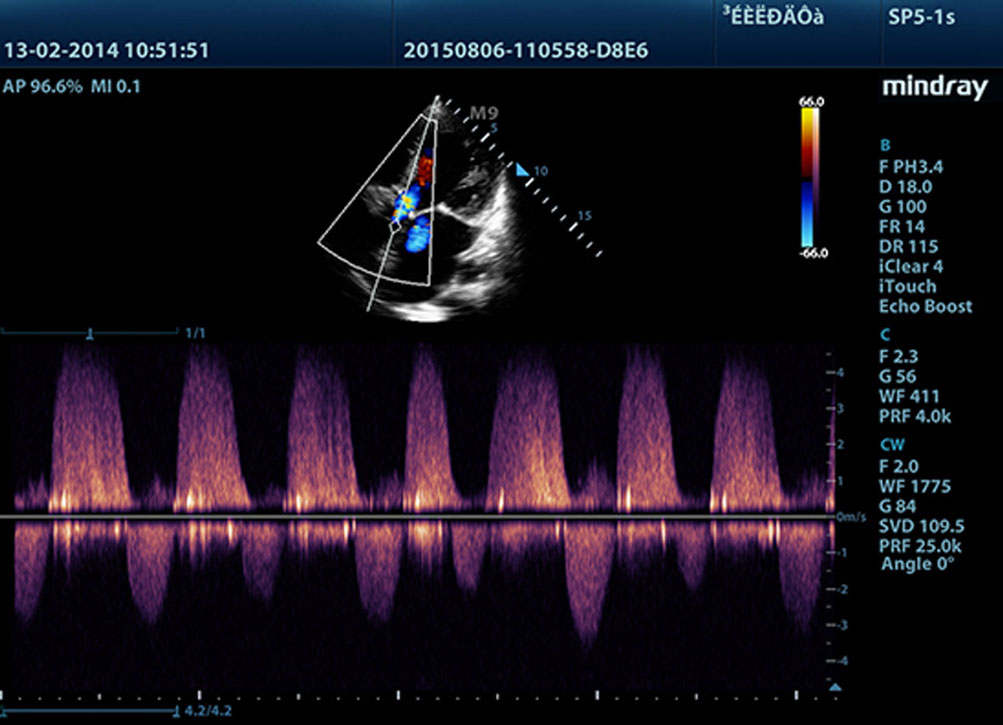

Echo Boost?

??? ?? ??? ?????? ??? ??? ?? ???? ??? ??? ?? ? ?? ??? ???? ?? ?? ??? ?????? ?? ??? ????? ???? ?? ?? ?? ?? ??? ?? ?? ?? ??? ???? ?????.

?? ??? ??(THI)

?? ????? ??? ? ?? ???? ???? THI? ?? ????? ??? ??? ?? ?? ???? ??? ???? ??? ??? ??????.